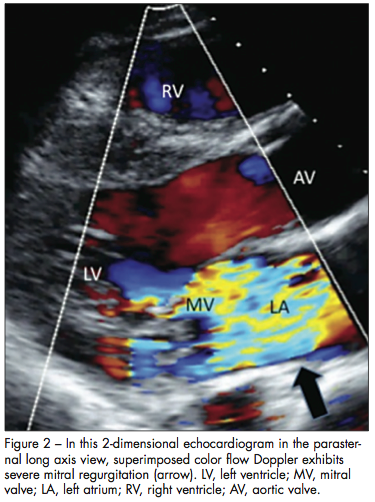

Echocardiographic images are obtained (Figures 1, 2, and 3). They demonstrate severe mitral regurgitation with a mobile, echogenic density on the posterior leaflet of the mitral valve (2.0 by 3 1.9 cm).